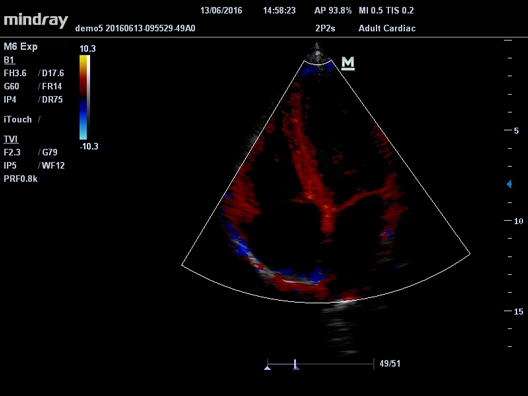

• Cardiac package для кардиологии

• Секторный фазированный датчик Mindray 2P2s